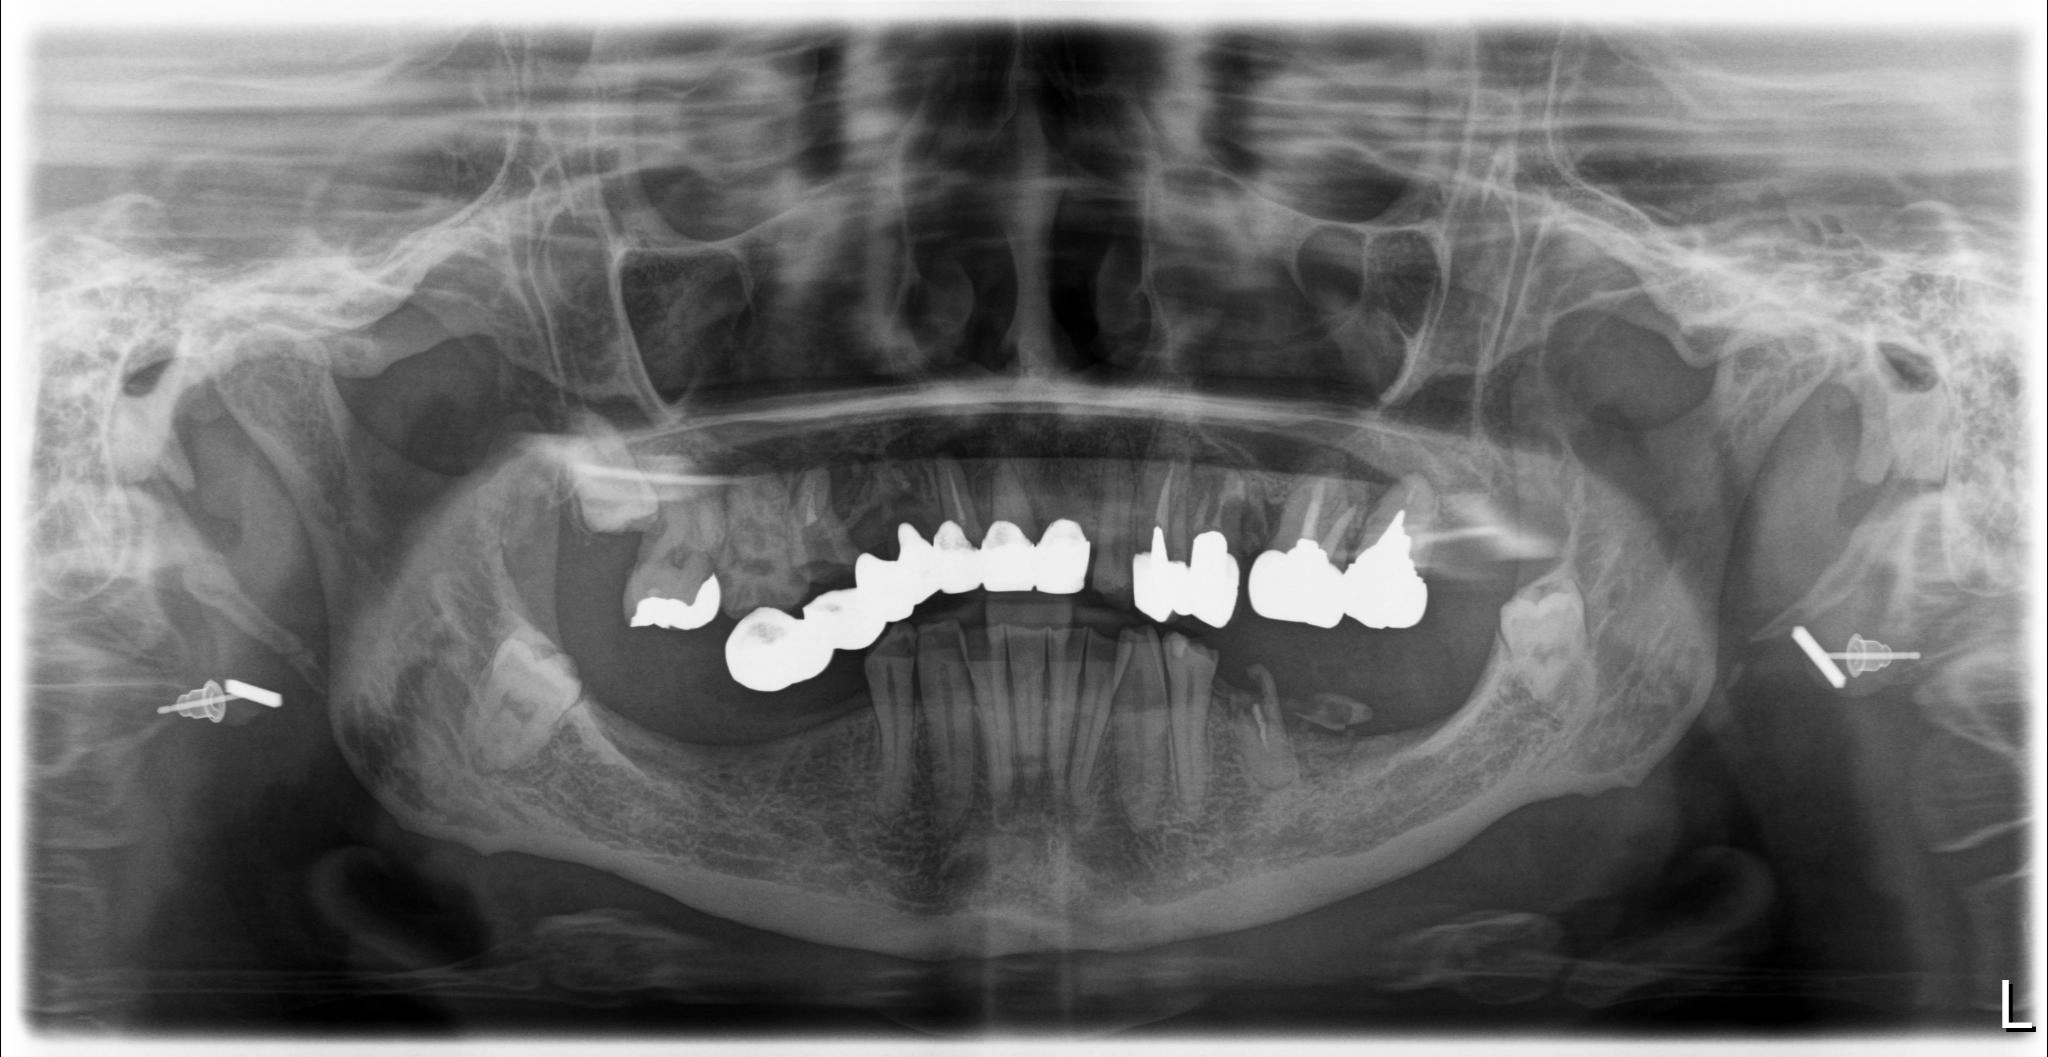

術前

長年歯について悩んでいました。歯がぐらつくことがあり、治療を行っていました。他院で入れ歯を作りましたが、噛み合わせが合わず、食事の際に噛みにくさを感じていました。

持病があるため、手術を受けられる状態か相談しに行くことにしました。